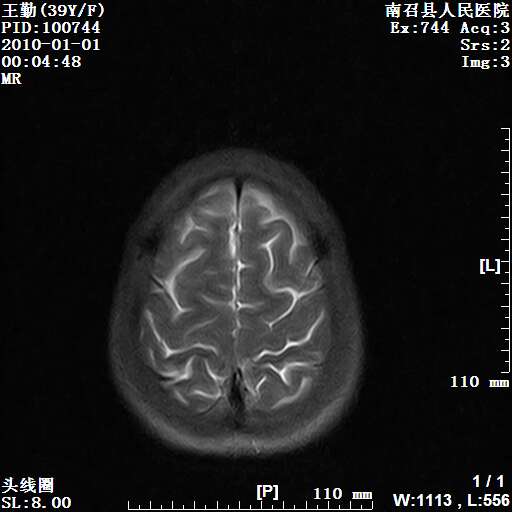

以下是引用随光逐影在2010-1-22 9:03:00的发言:[br]考虑左侧中颅窝(蝶骨翼区)脑膜瘤侵犯蝶骨翼并突入左侧眼眶。

以下是引用水过无痕在2010-1-22 14:55:00的发言:[br]一、定位:颅外占位;二、定性:恶性可能性大;三、组织来源:来源于左侧眼外直肌或其他部位;考虑为:横纹肌肉瘤>转移瘤>脑膜瘤.